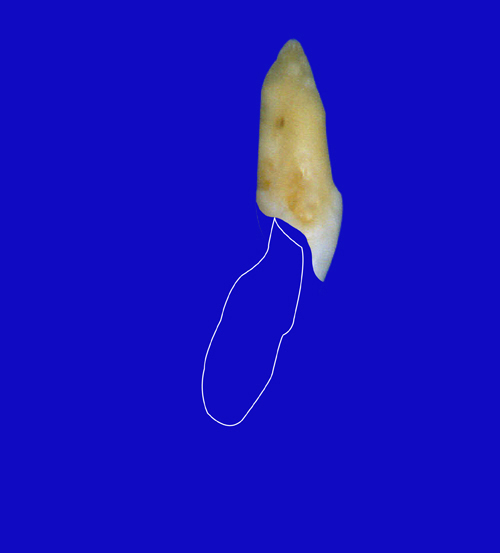

En ciertas áreas del saber humano, el lenguaje confuso o criptográfico Muchas son las técnicas elaboradas para lograr un desgaste selectivo, y numerosos autores han expuesto en su momento variadas formas de lograr una función oclusal fisiológica mediante el ajuste de la misma. Han pasado años desde entonces y, sin embargo, aún hoy, un altísimo porcentaje de profesionales “navega” por el mar de la confusión oclusal, dada la diversidad de conceptos y escuelas, sin lograr arribar a costa alguna donde poder anclar un conocimiento sólido sobre cómo tratar la oclusión Ya se esté realizando una simple obturación, endodoncia, incrustación, radectomía u ortodoncia, la lógica pocas veces, en la mayoría de los casos, vincula un tratamiento con otro, siendo el resultado final el mismo caos inicial; enmascarado por mucho tratamiento profesional. El ajuste oclusal es un medio inicial de proveer al sistema enfermo de: Dicha técnica, que puede ser terapéutica en sí misma; consta de dos etapas, a saber: 1) Ajuste Oclusal por Adición Mediante el estudio de la guía anterior, encargada de efectuar las Disclusiones durante las excursiones mandibulares, podremos observar si ésta es funcional o no. • Marcas de carácter continuo, si en ese recorrido se produce la Disclusión de los sectores posteriores y todo marcha correctamente. FIG 1-2 Si por el contrario observamos: • Marcas de carácter discontinuo, significa que dicha Disclusión se está efectuando por medio de una pieza dentaria posterior a la guía anterior. FIG 3-4-5 (FIGS. 3, 4 Y 5). En la figura 6 las flechas indican, en un caso clínico de análisis oclusal, la presencia de marcas discontinuas que indican Interferencias en Propulsiva. FIG 6-7 Y por último, si existieran: • Abrasiones de las áreas discluyentes en las áreas de diagnóstico de la guía anterior, deberemos aportar material a dicha zona para no permitir el choque lateral de las piezas posteriores (Ajuste Oclusal por Adición) En las imágenes 11 y 12 podemos observar la adición de composite en la punta de un canino derecho, previa la observación de la Faceta Parafuncional remarcada durante el análisis oclusal en el articulador. (FIGS. 8 A 12). 2) Ajuste oclusal por Sustracción o Desgaste Habiendo cumplido ya con la verificación de la funcionalidad de la Guía Anterior, comenzamos los desgastes en céntrica, a fin de lograr un único arco de cierre, guiado eficazmente por la Guía Anterior; es decir: la coincidencia entre Oclusión Habitual y Oclusión en Relación Céntrica. En este caso, intentar gastar dichos puntos, de ser posible sólo en las cúspides de corte o no fundamentales: • Crestas Triangulares Internas, Cúspides Vestíbulares Superiores • y un poco de las Crestas Triangulares Internas, Cúspides (FIGS. 13 A 16). Si la deflección es hacia el lado opuesto, se invierten los desgastes. En las migraciones hacia adelante, las únicas razones posibles están en los puntos estabilizadores (FIG. 17); es decir: -Vertientes Distales de los Rebordes Marginales, Triangulares (FIG 17) (FIG 18 A-B-C-D) Obsérvese cómo, en una boca prácticamente entera, comienzan a “desmoronarse” prismas adamantinos (FIG. 19), como consecuencia de un punto prematuro de contacto, ubicado en la posición de un estabilizador, que provoca la discrepancia horizontal postero-anterior causante de dicho efecto (FIG. 20). FIG 19-20 Dicho punto, será necesario ajustarlo antes de cualquier tratamiento en la zona ¿Cuáles serían las consecuencias si esos incisivos fueran implantados tal como es frecuente observar en múltiples congresos y cursos de implantología, donde el tema de la oclusión no es más que un cuadro polifacético y anecdótico? 14 15 16 17 Todo producto del adelantamiento mandibular Realizados ya los desgastes en céntrica, obteniendo de esta manera un único arco de cierre, es decir, oclusión en relación céntrica, debemos realizar el ajuste de las excéntricas, apoyando la acción de la guía anterior, para lo FIG 22 a. De un lado a otro de un mismo maxilar, la imagen es especular, o sea invertida. b. En hemimaxilares cruzados, la imagen es idéntica. Allí donde existan colisiones entre cúspides, se deberá crear un surco para que dicha cúspide antagonista migre a su través, tanto en el lado de no trabajo, como en el de trabajo y en el de propulsión. FIG 23 Es importante conservar esta parte del surco, ya que si no existieran, los contactos entre cúspides serían en superficie y no puntiformes (fig. 24). FIG 24 1. Obtener un único arco de cierre con coincidencia entre oclusión habitual y relación céntrica. 2. El cierre mandibular debe ser recibido sólo por la tabla premolar-molar. 3. Durante las excursiones funcionales es la guía anterior la que debe sufrir las fuerzas laterales. 4. De cumplirse estas dos premisas debemos obtener libertad de desplazamiento (no confundir con libertad en céntrica) a las piezas posteriores mediante la creación de surcos disclusivos. Examinadas ya las posibles migraciones mandibulares y los desgastes o aposiciones necesarios para poder ocluir en céntrica, es fundamental recordar que, previamente a todo tipo de ajuste, se ha hecho necesario ubicar a la mandíbula en relación céntrica. Para ello debemos utilizar el propio funcionalismo muscular 22 FIG 25 Y esto no significa otra cosa que: piezas dentarias estables en todos los planos del espacio, ATM centrada en la cavidad glenoidea, periodontos sin tensión, músculos en la dimensión de elongación adecuada para un fisiologismo Paz absoluta en la intimidad del Sistema Estomatognático. Y así, como corolario final, es posible establecer una regla de oro similar en importancia a la conocida formula: Forma = Función Ésta es: FIG 26 FUNDAMENTOS NEUROFISIOLÓGICOS DEL REGISTRO DE OCLUSIÓN EN RELACIÓN CÉNTRICA ( ORC) MEDIANTE EL USO DE LAMINILLAS DE LONG CUADRO

Esta migración generalmente se acompaña de anomalías en el sector anterior (FIG. 18).

anterior, ya que si no liberamos la causa, el efecto se seguirá produciendo y, a

pesar de que la abrasión de0estos incisivos superiores es apenas el comienzo de una futura bruxomanía, invito al lector, sea éste especialista en prótesis, operatoria dental, cirugía bucal, etc., a pensar: